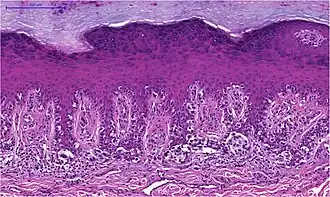

Superfiziell spreitendes Melanom

Das superfiziell spreitende Melanom entsteht in bedeckter, üblicherweise nicht dem Sonnenlicht ausgesetzter Haut. Vorausgegangene Sonnenbrände in der Kindheit und wiederholte Sonnenlichteinstrahlung im Erwachsenenalter sind dennoch ursächlich bedeutsam. Der Tumor wächst überwiegend horizontal zunächst als auf die Epidermis beschränktes Melanoma in situ. Die epidermale Komponente ist zumeist breit und unscharf begrenzt, aber auch scharf begrenzte Läsionen bei klinisch unregelmäßiger Kontur kommen vor.

Die Melanozyten haben große Zellkerne, die häufig auch vergrößerte Nukleolen aufweisen. Mitosen sind in der epidermalen Komponente selten. Das Zytoplasma ist üblicherweise weit und der Pigmentgehalt kann innerhalb einer Läsion stark wechseln. Die Tumorzellen breiten sich einzeln oder in unregelmäßigen, teils miteinander verbundenen Nestern in der Epidermis aus und folgen dabei Adnexstrukturen. Typisch für das superfiziell spreitende Melanom ist das als pagetoid bezeichnete Wachstumsmuster: atypische Melanozyten finden sich nicht nur entlang der Junktionszone, sondern verteilt über die ganze Breite der Epidermis bis in oberflächliche Zelllagen.

Die dermale Komponente superfiziell spreitender Melanome ist in der Regel asymmetrisch aufgebaut. Eine Ausreifung der Melanozyten fehlt und es finden sich Mitosen. Selten zeigen sich nekrotische (abgestorbene) Melanozyten. An der Basis des Tumors und eventuell auch zwischen den Tumorzellen besteht ein hauptsächlich lymphozytäres Entzündungsinfiltrat.[44]

- Superfiziell spreitendes Melanom

-

Unregelmäßige melanozytäre Nester, hier überwiegend entlang der Junktionszone. -

Einzelmelanozyten und unregelmäßige melanozytäre Nester auch in mittleren Schichten der Epidermis